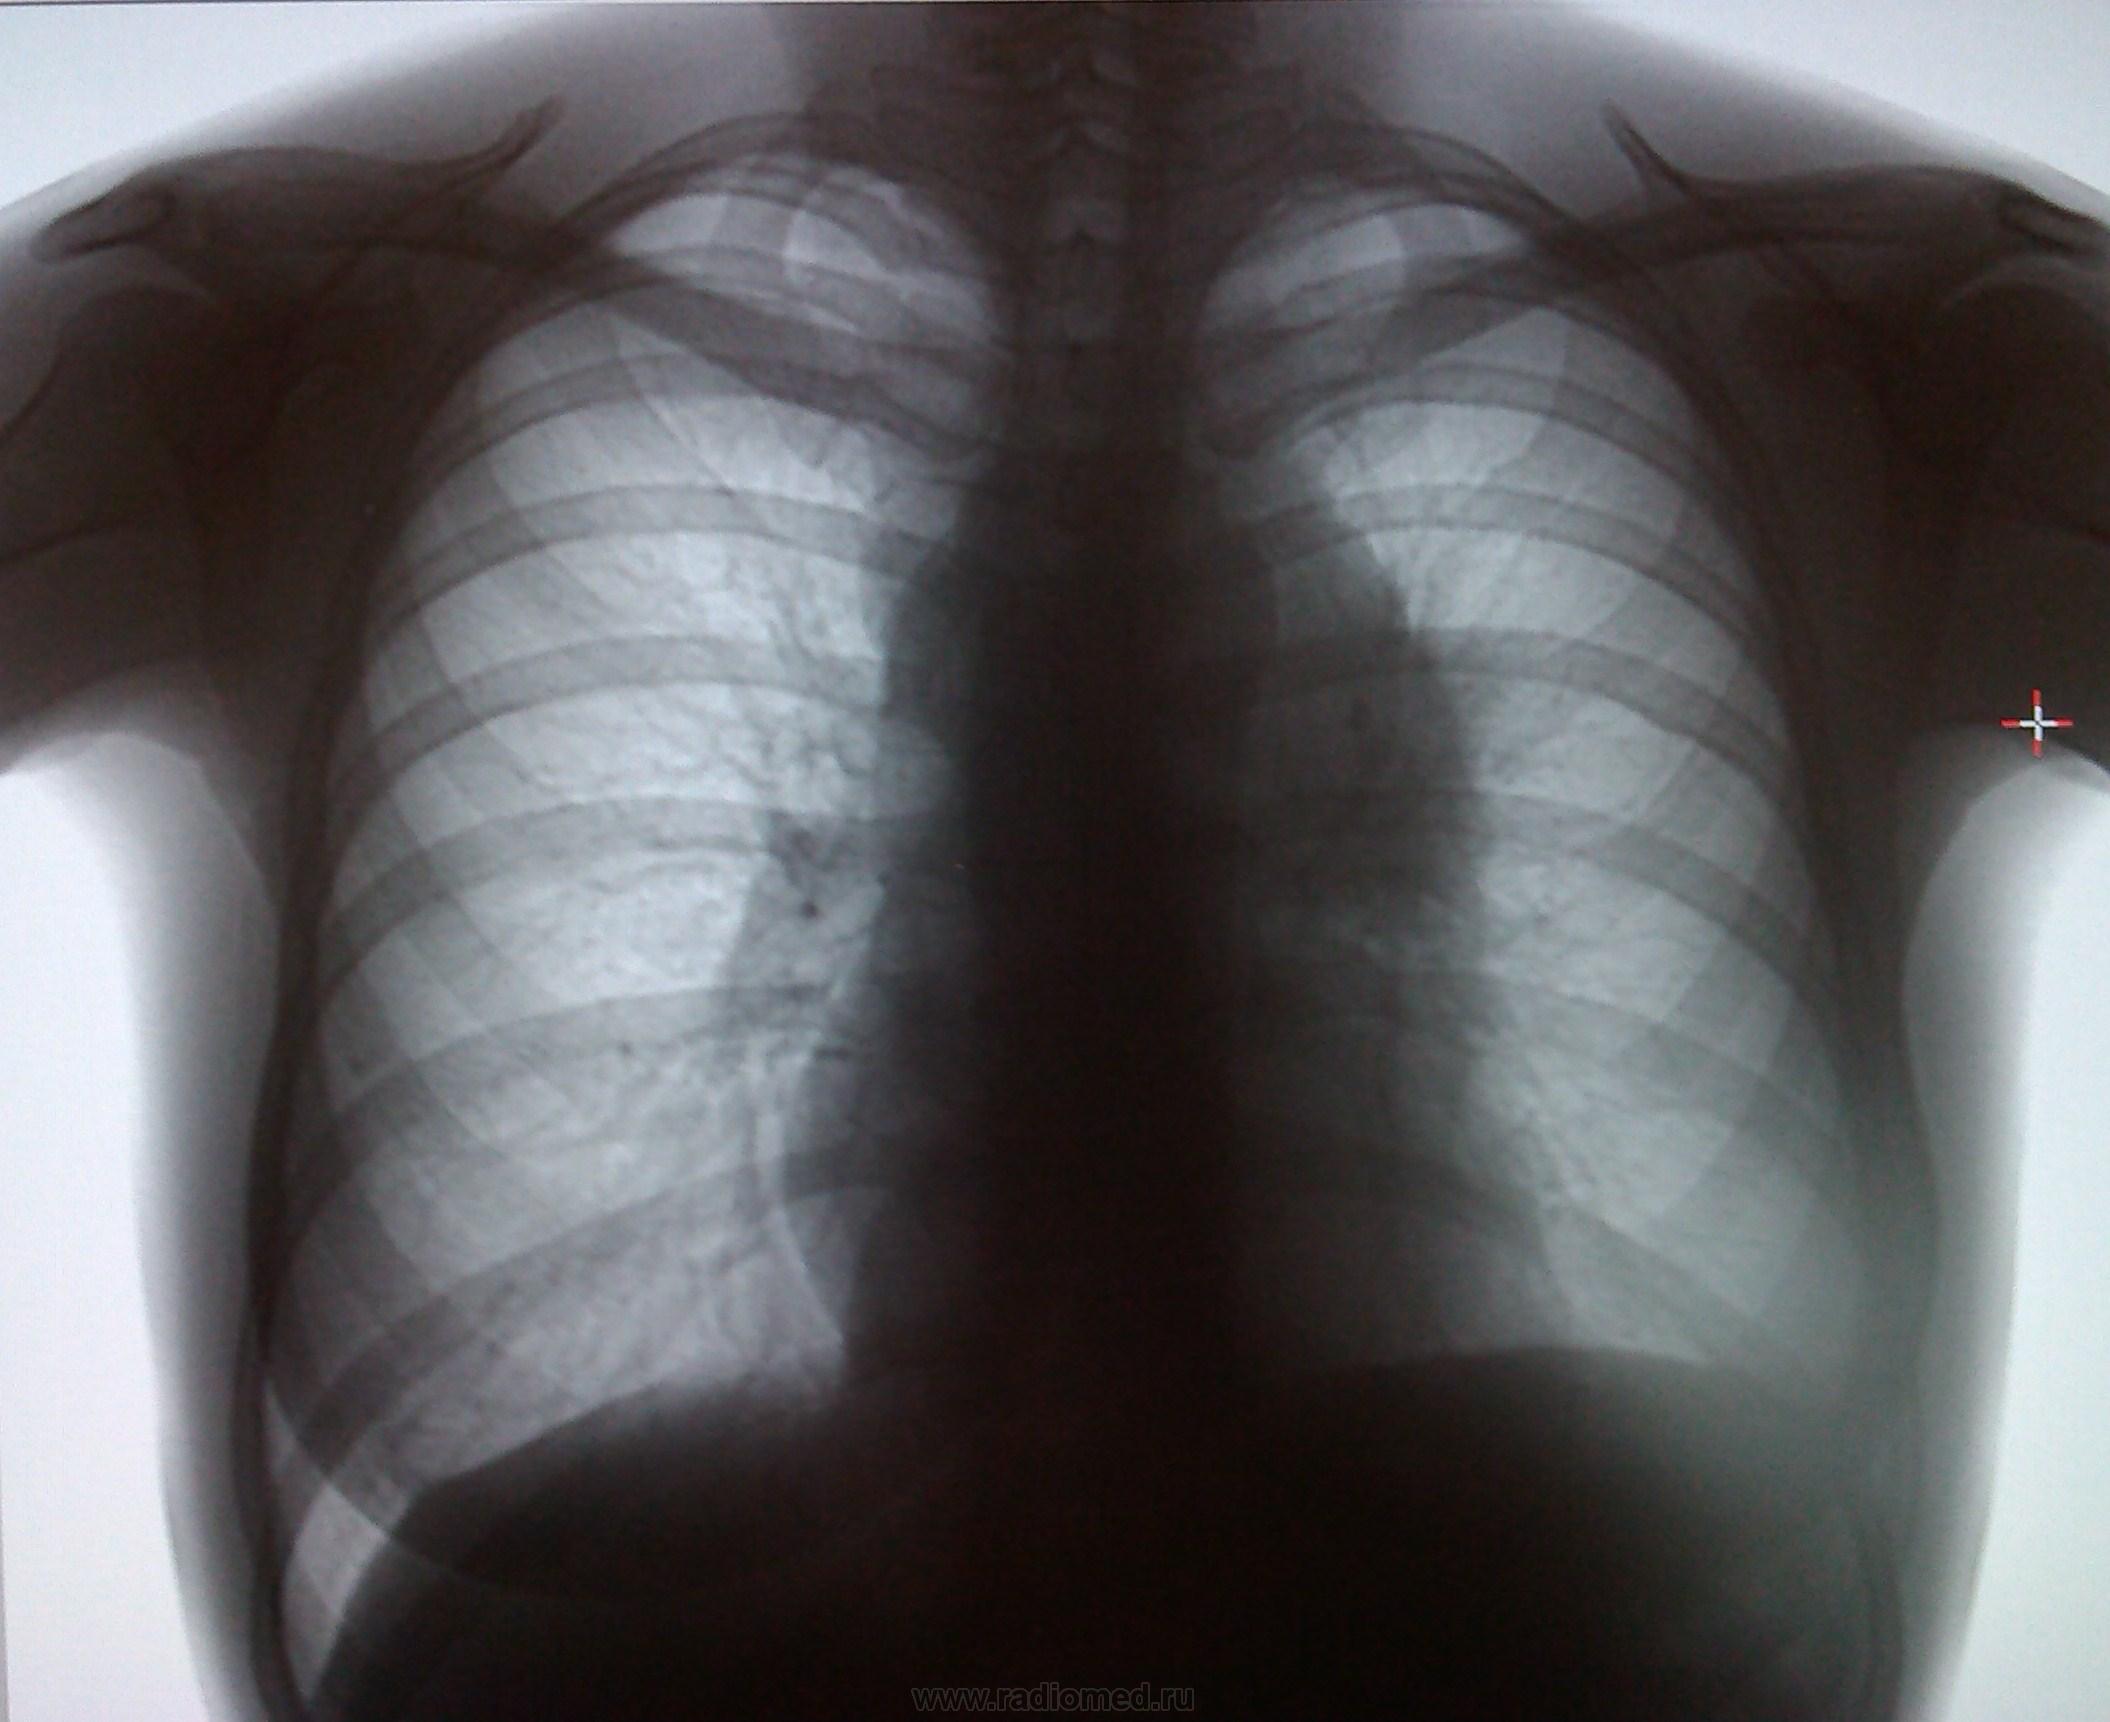

Снимок легких при туберкулезе является важным методом диагностики этого заболевания. На рентгеновских снимках можно увидеть изменения в легких, которые свойственны туберкулезу.

Фотографии снимков легких при туберкулезе

В данной статье представлены многочисленные фотографии снимков легких при туберкулезе, чтобы помочь вам понять, как выглядят изменения легких на рентгеновских снимках при этом заболевании.